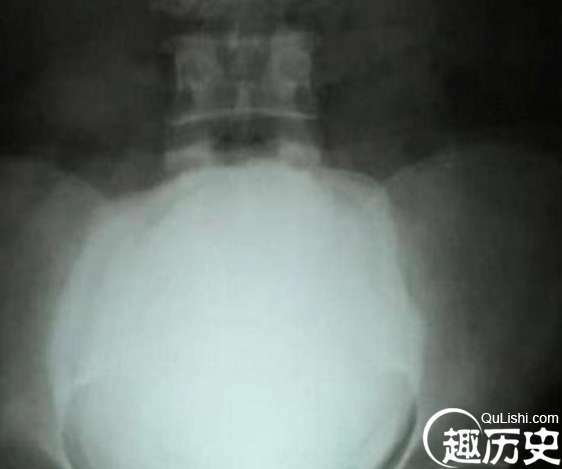

在印度,有一位男子叫帕特尔,今年50岁。近日在医生的帮助下,成功取出体内一颗直径达10厘米的大结石,结石重达2.8斤,一举打破7年前,同样是一位印度男子创下的记录,那位男子患有癌症,体内出现了一个2.4斤的结石。

医生表示,这块结石的起因是因为男子在1997年的时候发生的一起车祸,当是虽无大碍,但尿道却受损了,日积月累之下,钙质过度的堆积,才形成了这一个结石。

这件事来的很突然,有一天晚上,帕特尔的肚子就突然疼起来了,犹如阑尾炎一般,但当他去到医院后,经过医生的检查,才知道了这块结石的存在。手术历经一个多小时,由于医生事先已经给帕特尔拍了X光,所以手术非常的顺利。